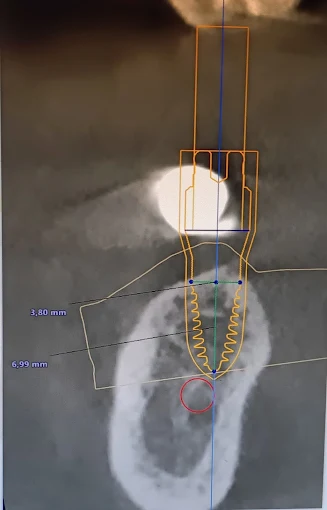

Zahnimplantate aus deutscher und schweizer Herstellung mit bis zu 98% Erfolgsquote, auch ohne Knochenaufbau möglich.

Digitale Röntgentechnik

Maximale Detailschärfe in Sekunden bei minimaler Strahlenbelastung.